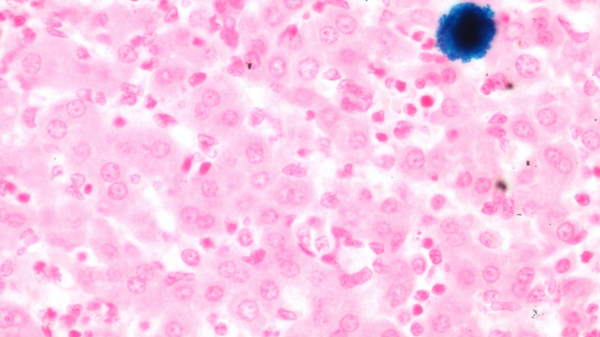

EMATOLOGIA. Identificati due trasportatori che riforniscono le cellule malate di un aminoacido che rende inefficace la terapia farmacologica.